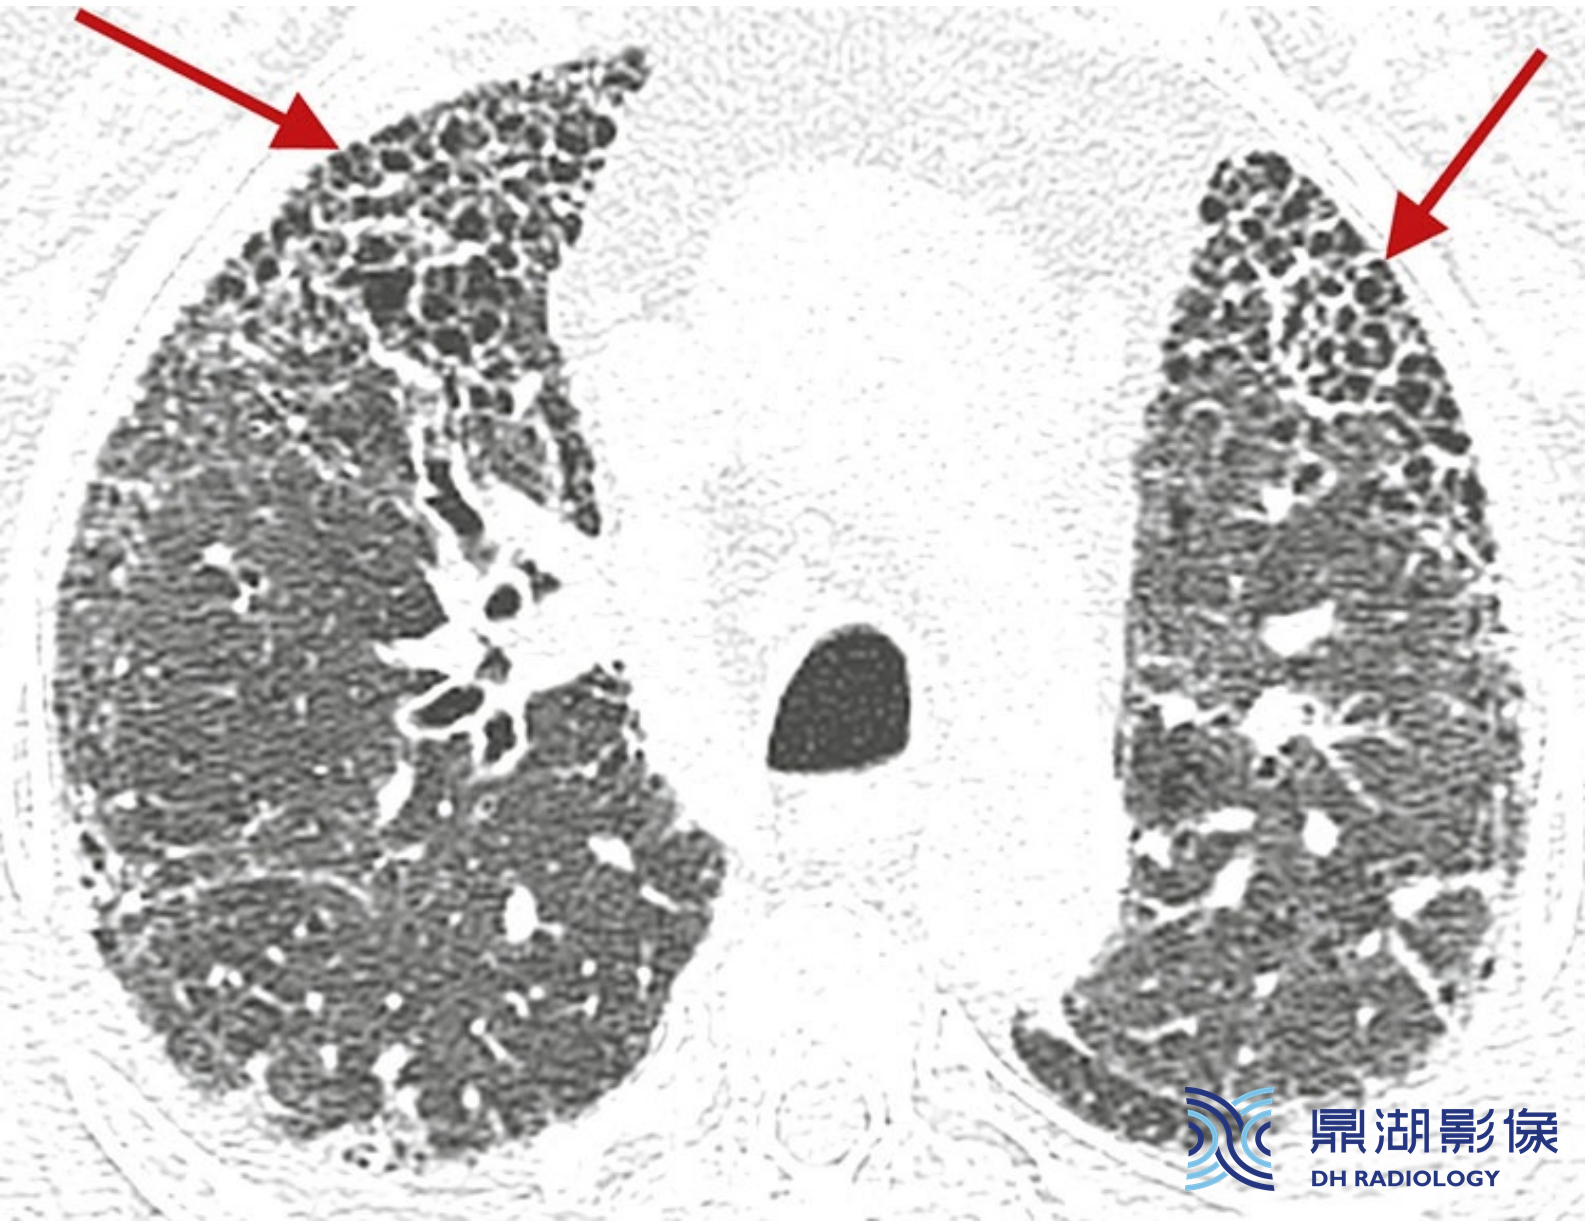

间质性肺水肿伴小叶间隔增厚的典型表现。

多发的、平滑的、薄的、相互连接的线条影勾勒出肺小叶的多边形结构,其特征性大小、形状及小叶中央动脉有助于识别。

这些线条影是勾勒出肺小叶边界的小叶间隔。肺水肿是小叶间隔平滑增厚的最常见病因。也可见肺裂增厚。

鉴于肺小叶典型的大小和多角形外观,当HRCT可识别的肺小叶表现为网状不透明的轮廓时,则可诊断为小叶间隔增厚(IST)。小叶中央动脉可表现为肺小叶的多边形结构中央的小点,且因周围水肿而显得更为明显。

由于上叶的间隔发育最佳,水肿所致的小叶间隔增厚常见于上叶。胸膜下的水肿相当于小叶间隔增厚,可表现为肺裂增厚。